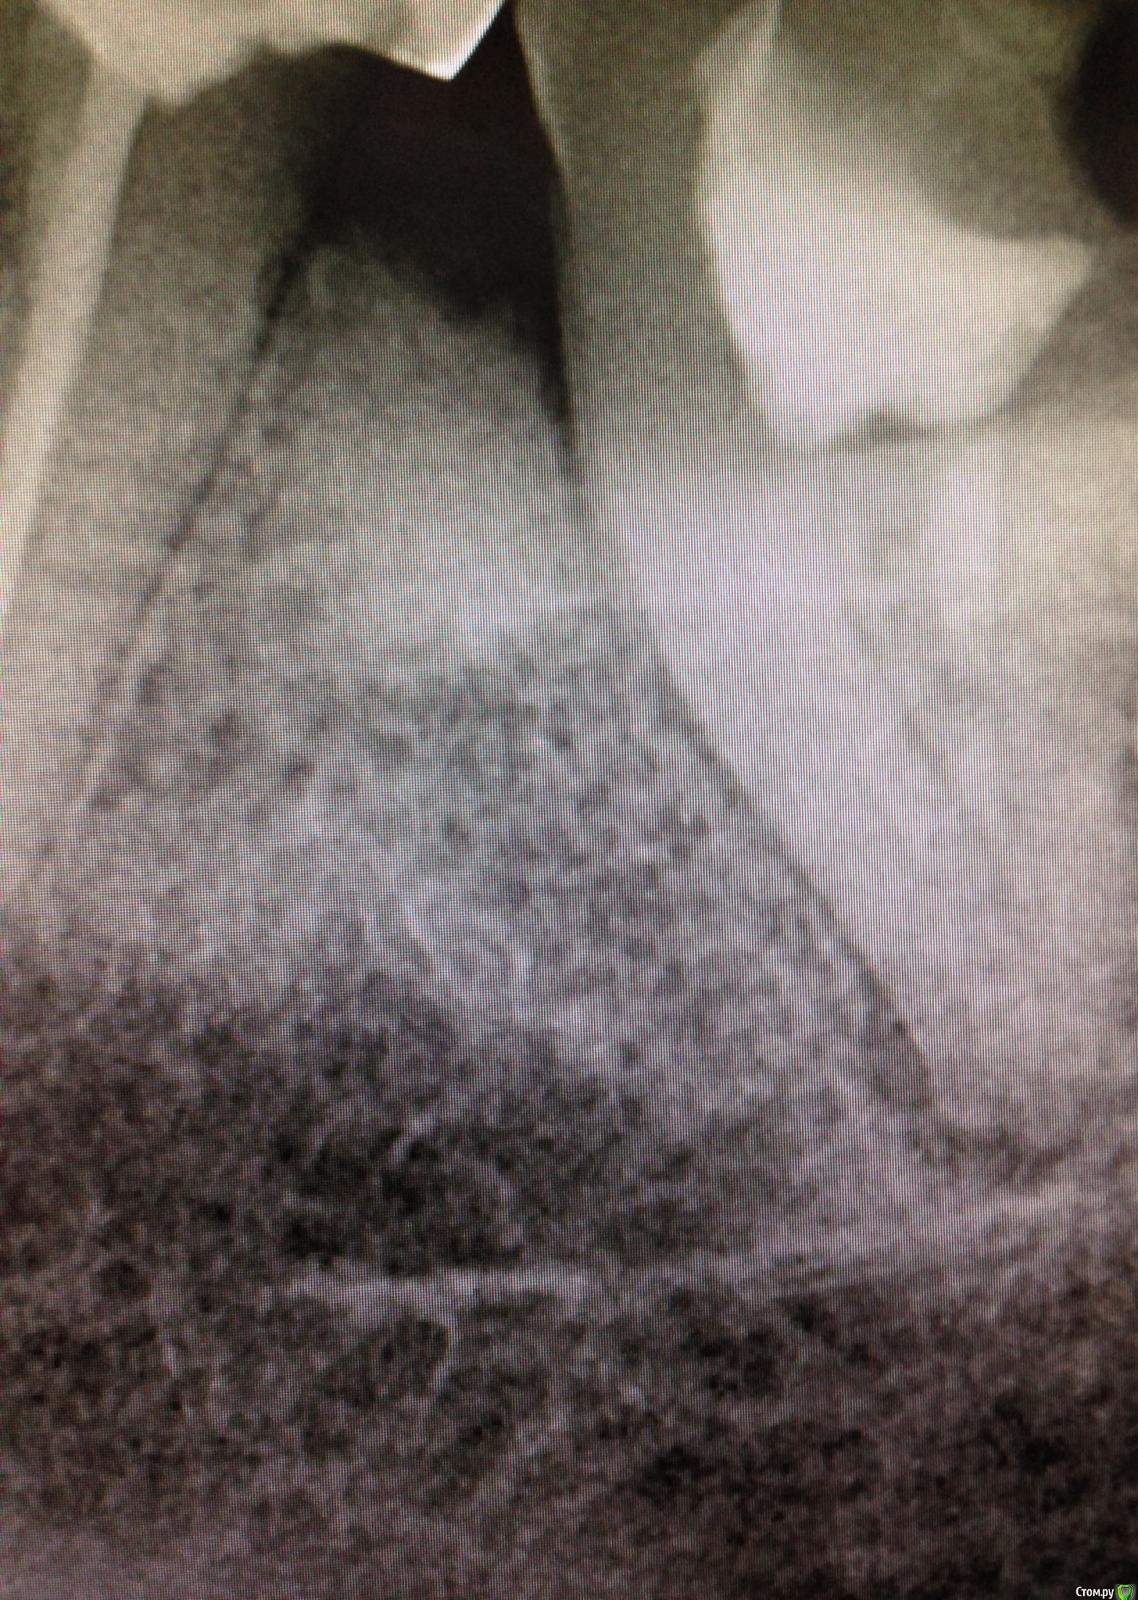

SSTi Опубликовано 9 декабря, 2014 Автор Поделиться Опубликовано 9 декабря, 2014 Чуть обновимся. Пульпитный 36. Медиальные профайлы 35.04. Дистальный 40.04. ОХАП 37. Резорцин старый. Через кальций. 12 хап. 13 пульпит. 60 упор 5 Ссылка на комментарий